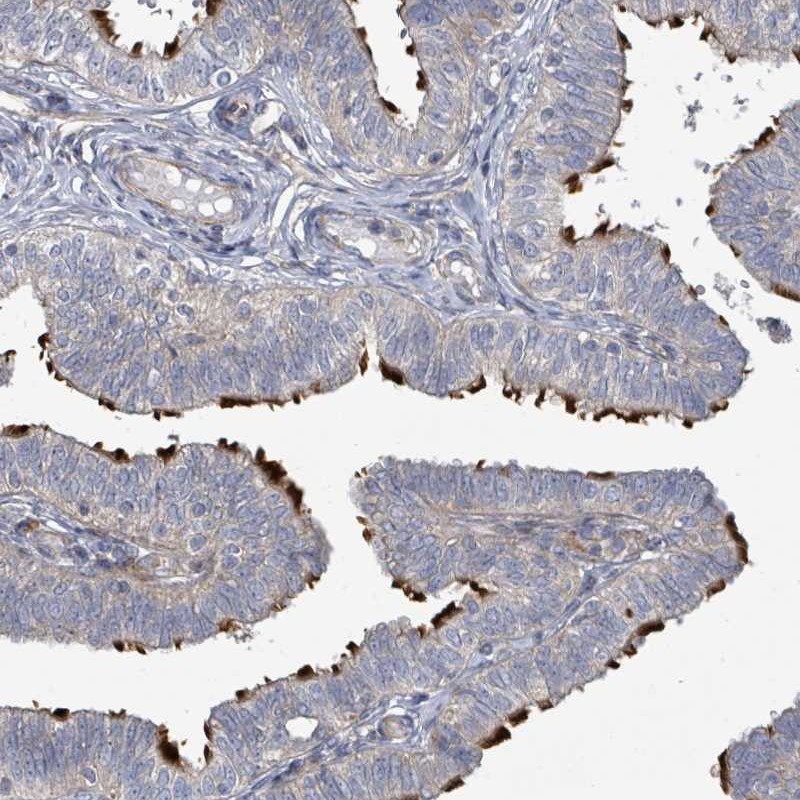

Immunohistochemical staining of human fallopian tube shows distinct positivity in cilia.